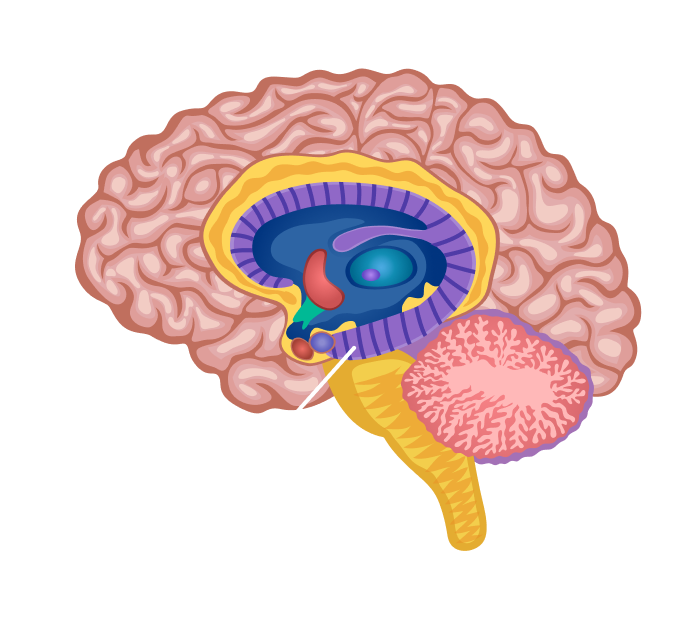

Легкие рисунки головного мозга: Пошаговые инструкции